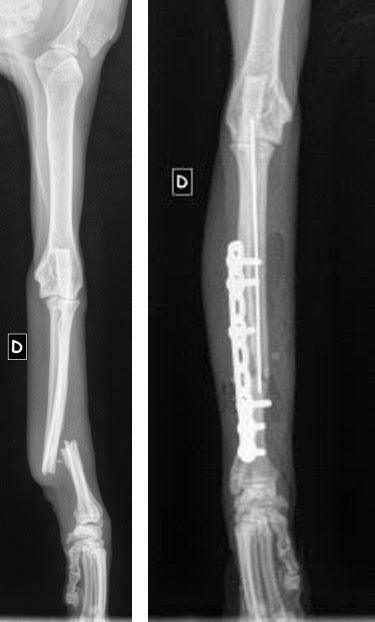

Tess est une jeune chatte d'à peine un an qui a eu la chance de croiser sur son chemin un certain monsieur, sur la route de Montbert. Elle ne marchait que sur 3 pattes alors ce monsieur l'a déposée dans un cabinet vétérinaire et le verdict tombe : fracture ouverte datant de plusieurs jours. La blessure est telle que l'amputation n'est plus une option... Le cabinet a tenté de retrouver les propriétaires de cette chatte adorable, en vain. Ils ont également contacté plusieurs associations et nous avons répondu présent pour financer cette opération urgente et prendre en charge Tess par la suite. Elle est actuellement en convalescence dans l'une de nos familles d'accueil qui n'a pas hésité une seconde malgré le manque de place ! Elle sera prochainement proposée à l'adoption après sa stérilisation. Nous ne lançons pas d'appel aux dons à chaque opération que nous prenons en charge mais sachez que votre générosité sert à préserver leur vie, à les sauver pour certain et ce fut le cas pour Tess. Merci à ce monsieur de lui être venu en aide et merci aux donateurs sans qui nous ne pourrions continuer nos actions !